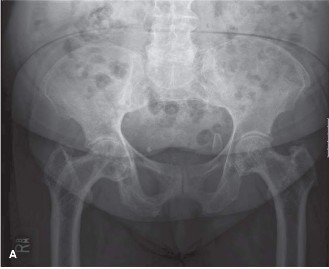

A 71-year-old male is brought to the ER after sustaining a motor vehicle crash. During routine trauma workup,…